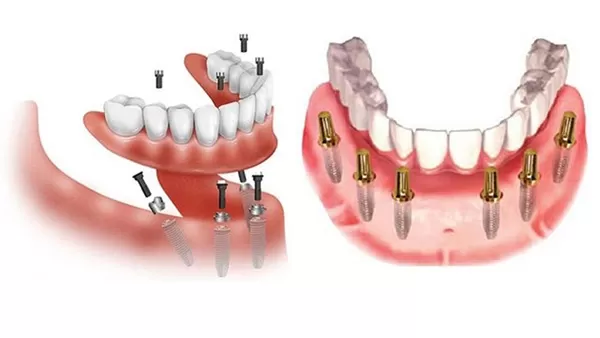

Những trường hợp bị mất toàn bộ răng hàm trên, hoặc răng hàm dưới, hoặc mất cả hai hàm, bác sĩ sẽ chỉ định cấy Implant All-on-4; All-on-6.

Kỹ thuật cấy Implant All-on-4; All-on-6, còn gọi là Implant toàn hàm cho phép người bị mất nhiều răng hoặc mất răng toàn hàm có thể phục hồi hoàn toàn chức năng ăn nhai cũng như độ thẩm mỹ. Đây là kỹ thuật phục hồi toàn bộ răng mất trên một hàm bằng 4 hoặc 6 Implant. Một hàm răng sứ cố định trên 4 hoặc 6 implant gồm 10 – 12 răng, vừa đảm bảo chức năng ăn nhai và thẩm mỹ, vừa tiết kiệm chi phí cho khách hàng.

Phục hình cố định trên All-on-4 và All-on-6 sẽ có số răng là 10-12 răng trên 1 hàm. All-on-4 (thường đặt ở các vị trí răng số 2 và 5), được chỉ định khi không đủ xương ở vị trí những răng hàm phía sau để đặt thêm Implant.

Trong khi đó All-on-6 (thường đặt ở các vị trí răng số 2, 4, 6) được chỉ định khi xương của vùng răng hàm còn đủ. All-on-6 sẽ cho chức năng tốt hơn: nhiều Implant hơn, nhiều răng hơn và nâng đỡ tốt hơn. Với kỹ thuật này, cần 2 giai đoạn điều trị, cách nhau 6 – 8 tháng hoặc lên tới 1 năm tùy trường hợp cụ thể.